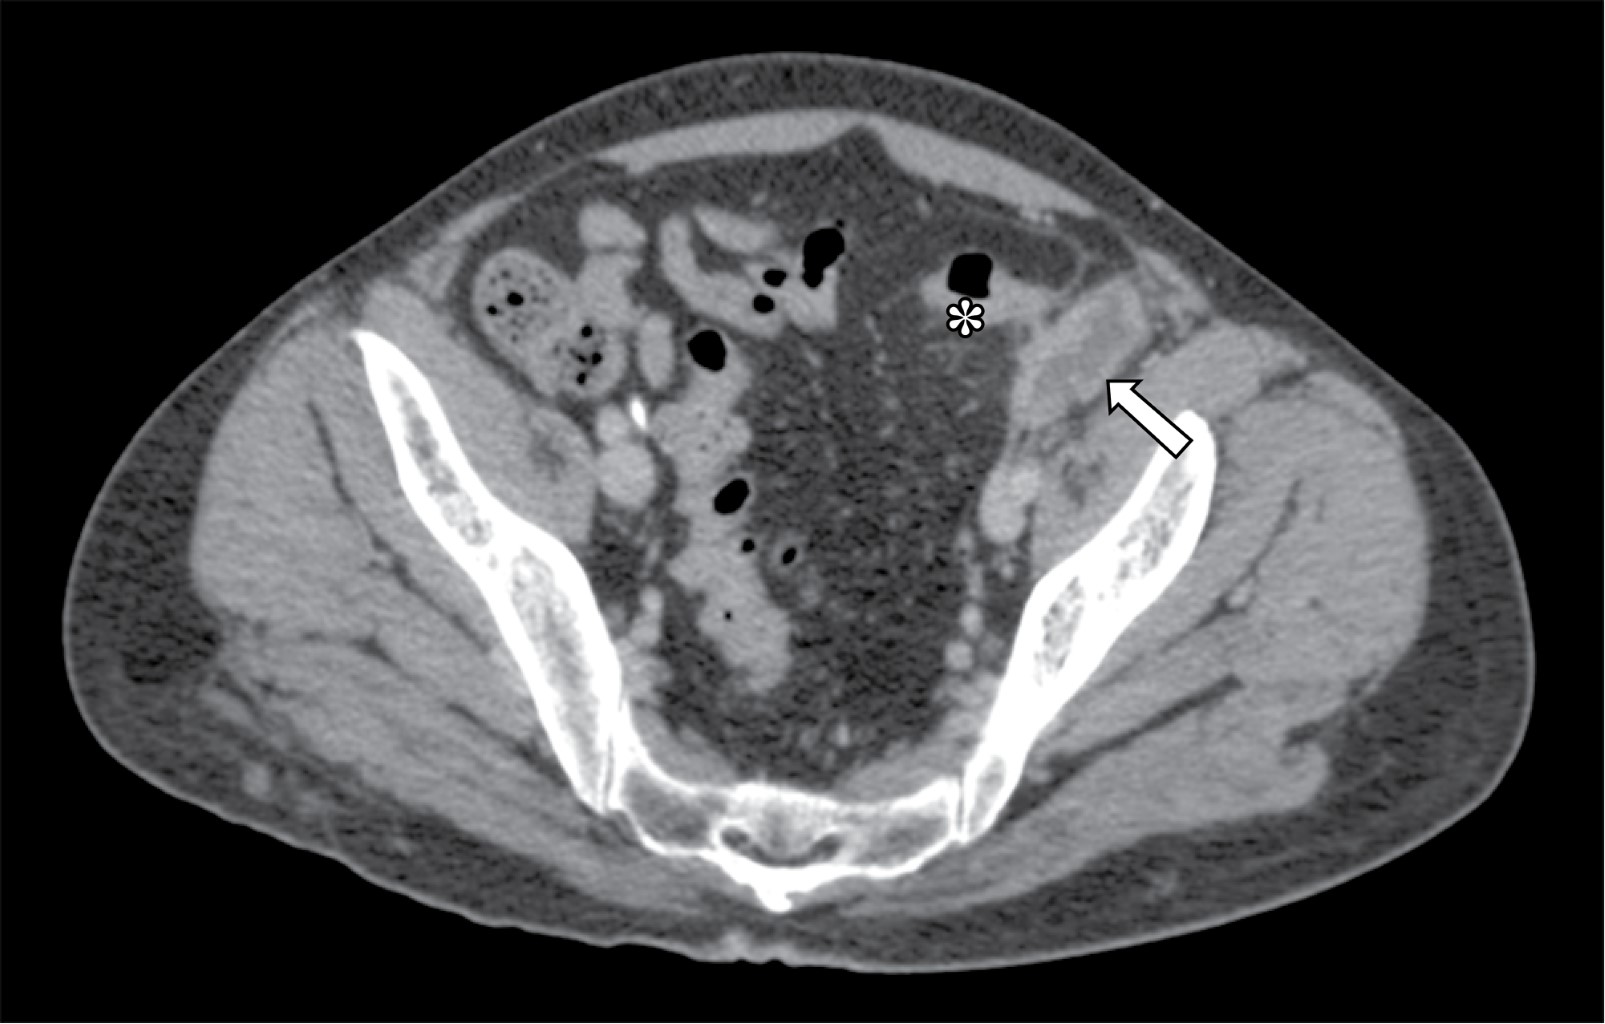

Paciente masculino de 54 años quien inició el 20 de abril de 2020 con dolor abdominal de predominio en fosa iliaca izquierda; se solicitó estudio tomográfico y se estableció el diagnóstico de diverticulitis aguda grado Hinchey Ib (absceso pericólico) en otra clínica y se manejó con ceftriaxona 1 g intramuscular cada 12 horas por cinco días. Dos semanas posteriores al término del tratamiento presentó exacerbación del cuadro con incremento del dolor y alza térmica cuantificada hasta 37.7 oC, sin otra sintomatología acompañante. Como comorbilidades refirió únicamente trastorno depresivo mayor en tratamiento con clobazam. Como antecedente de importancia destacaba plastia inguinal izquierda con colocación de malla por vía laparoscópica dos años previos al inicio de los síntomas. A la exploración física sus signos vitales eran presión arterial (TA) 130/80 mmHg, frecuencia cardiaca (FC) 90, frecuencia respiratoria (FR) 16, temperatura 37.1 oC; abdomen blando, depresible, doloroso a la palpación media y profunda de fosa iliaca izquierda, sin datos de irritación peritoneal y sin cambios en la coloración de la piel. En los estudios de laboratorio de ingreso: leucocitos séricos 6.2 × 103/μL, neutrófilos absolutos 4.22 × 103/μL, proteína C reactiva ultrasensible 3.06 mg/dL, velocidad de sedimentación globular 36 mm/h y procalcitonina sérica 0.05 ng/dL. Una tomografía de abdomen reveló una colección hipodensa localizada en receso paracólico izquierdo (Figura 1), cuyas características tomográficas eran sugestivas de un proceso infeccioso. Tras la administración de contraste endovenoso y transrectal se observó reforzamiento de la pared de la colección sin evidencia de comunicación entre la colección y el colon (Figura 2). Se realizó drenaje percutáneo de la colección guiado por tomografía obteniendo 10 mL de material hematopurulento dejando catéter Dawson Mueller 8.5 Fr; el cultivo aeróbico reportó crecimiento de Serratia marcescens sensible a carbapenémicos. Completó cinco días de tratamiento con meropenem 1 g intramuscular cada ocho horas y fue egresado previo retiro del drenaje. Reingresó tres semanas después de su egreso para el retiro de la malla. Realizamos un abordaje en línea media infraumbilical, incidiendo hasta el espacio preperitoneal sin entrar a cavidad (Figura 3). Se disecó el espacio preperitoneal izquierdo de forma roma hasta el nivel de la espina iliaca anterosuperior ipsilateral, visualizando y respetando los vasos epigástricos profundos, mismos que se rechazaron superiormente junto con fibras del recto abdominal (Figura 4). Se extrajo malla de poliéster autoadherible, la cual se encontraba plicada y distorsionada (Figura 5). Por último, se lavó el espacio preperitoneal con un litro de microdacyn, se colocó drenaje cerrado 19 Fr, se afrontó aponeurosis anterior con surgete tipo Small bites utilizando sutura 0 de muy lenta absorción y se colocaron grapas en piel. El procedimiento se llevó a cabo en un tiempo de 60 minutos y un sangrado cuantificado en 30 mL. Cursó su postoperatorio sin eventualidades y fue egresado al día siguiente. El drenaje se retiró a los cinco días en consulta externa.

Figura 2